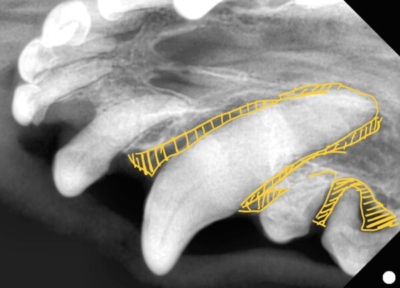

まず、全身麻酔をかけて歯科レントゲンを全ての歯で撮影します。

上顎の切歯のレントゲン

黄色斜線部分が歯の周りの骨が溶けてしまったところ。

このようにひとつひとつの歯を評価していきます。

右上の犬歯

黄色斜線部が歯周病で周りの骨が溶けてしまっている状態。口腔鼻腔ろうになっていた。

歯科レントゲンでも犬歯の一部に欠損があるのがわかりますね。これは頭部レントゲンで撮影した部分と一致します。

左上顎の犬歯です

こちらも残念ながらかなり深い骨の喪失があります。